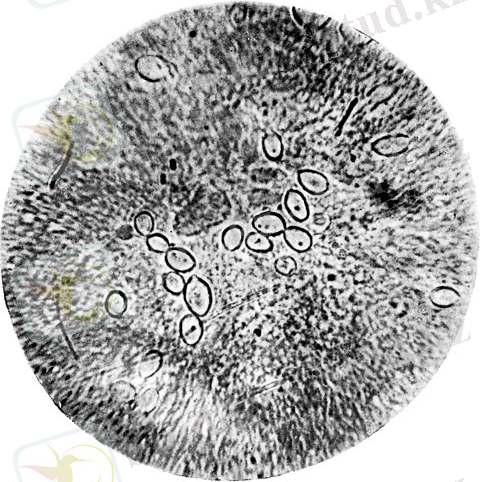

Этиологиясы. Қоздырғышы - Toxoplasma gondіі, қарапайымдылардың споралылар класына жататын облигатты жасушаішілік паразит, морфологиясы жарты ай немесе созыңқы апельсин үлесшесіне ұқсас болады (toxo - грекше арка деген сөз) . Бір шеті үшкірленген, екіншісі - жұмырланған, ұзындығы - 4-7 мкм. Цитоплазмасы Романовский-Гимза әдісімен ашық көк түске, ядросы - қызыл-күлгін түске боялады. Токсоплазмалар барлық сүтқоректілердің эритроциттерінен басқа жасушалардың бәрінің ішінде өсіп-өніп көбейеді, тіндерде аурудың жіті кезінде табылады. Вегетативтік түрінің (трофозоиттардың) бір жасуша ішінде шоғырлануын жалған циста (псевдоциста) дейді. Тіндерде (мидың, көздің, бұлшық еттің т. б. ) токсоплазмалар тығыз қабаттан қоршалған нағыз цисталар құрайды. Олар сыртқы ортада төзімді болады.

Морфологиялық ерекшеліктері және даму циклі . Ие жасушасының ішінде орналасқан токсоплазмалар - эндозоидтар деп аталады. Эндозоид жарты ай пішіндес (өлшемі 4-7 х 2-4 мкм) . Оның бір ұшы үшкір, екінші ұшы дөңестелген. Орталығында ядросы бар. Үшкірленген ұшында микроскоппен қарағанда коноидкөрінеді, ол сорғышқа ұқсас. Коноид паразиттің жасушасына бекітіліп енуі үшін қажет. Эндозоид жыныссыз көбейеді, ұзыннан бөліну немесе эндогония жолымен жүреді. Бірнеше бөлінулерден кейін ие жасушасының цитоплазмасында көптеген токсоплазмалар пайда болады да, мембрананы созады. Токсоплазмалардың жасуша мембранасының астында жиналуын псевдоциста деп атайды. Зақымданған жасуша өлгеннен кейін токсоплазмалар жаңа жасушаға енеді. Созылмалы токсоплазмозда псевдоцистамен қатар шынайы цисталар түзіледі. Бұл әдетте, токсоплазмалардың тірі жинақтары (100 мкм-ге дейін), қалың қабат астында бірнеше жүз токсоплазмалар жиналады. Жасушадағы цисталар тіршілігін бірнеше жылға дейін сақтауы мүмкін. Иесінің паразиттік тіршілігіне көнуі және түрдің жыныссыз көбеюі арқылы ұзақ уақыт тіршілік етуге бейімді. Алайда, түрді сақтап қалу үшін токсоплазма әр кезде жынысты жолмен де көбейеді. Ол мысықтектес жыртқыштар денесінде жүзеге асырылады (әсіресе, үй мысықтарында) . Ол үшін жіңішке ішек эпителиінде алдымен бір эндозоидтардан макрогаметоциттер түзіледі, ал кейін макрогаметалар, ал басқа біреулерінен микрогаметоциттер, әрі қарай микрогаметалар; популяциядан кейін зигота түзіледі, оның қалың қабығы бар. Мұндай форма ооциста деп аталады.